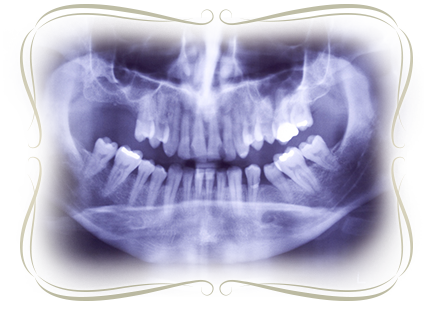

歯科用CTは顎顔面に特化しており、立体的に撮影・確認することが出来るため治療前に十分な診断が可能です。院内に完備しておりますので、治療時間の短縮にもつながります。

従来のフィルム型レントゲン撮影と比べ放射線量が約1/10と大変少なく、お身体に優しいレントゲンです。モニターに映しすぐに確認できるので、時間も短縮されます。

顔面・頭部のレントゲン写真が撮影でき、骨格の成長の変化や歯の移動を観察できます。矯正治療には欠かせない機器です。